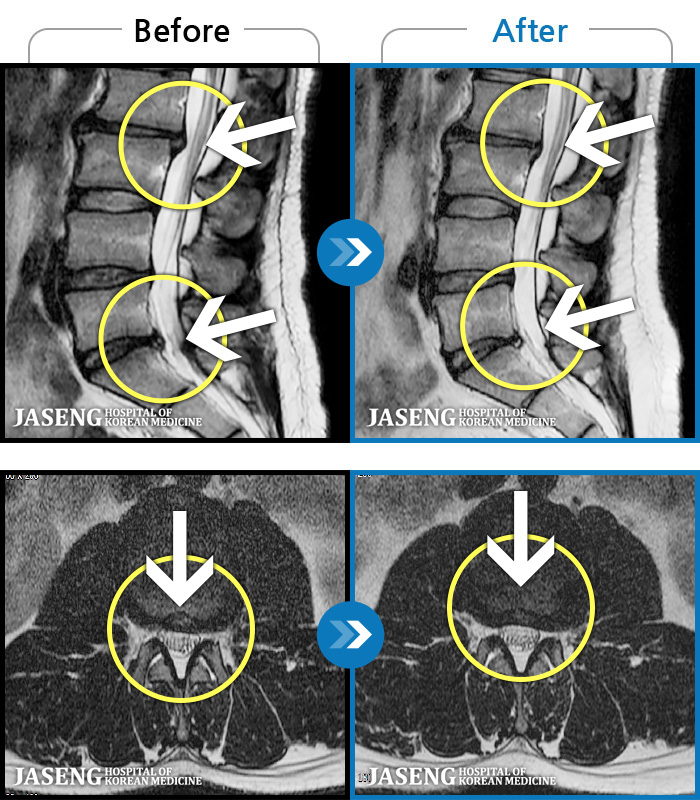

MRI ġ

1,237 MRI ũ ʸ Ȯϼ.

[Ȼ_㸮ũ] 㸮 ְ ٸ ȱⰡ .

No.1237

ȸ 2,757

2025.10.02